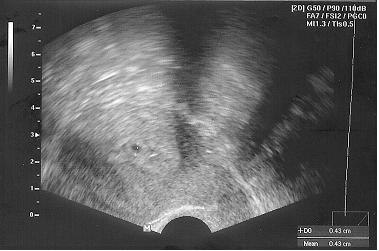

A képek, amiket ígértem, remélem nem bánják a többiek sem.